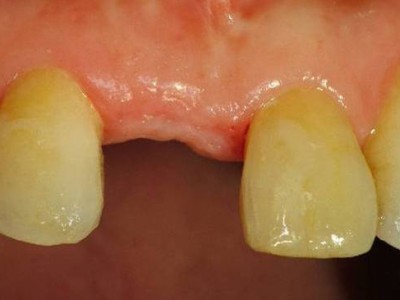

A+ 임플란트의 다양한 케이스를 확인해보세요.